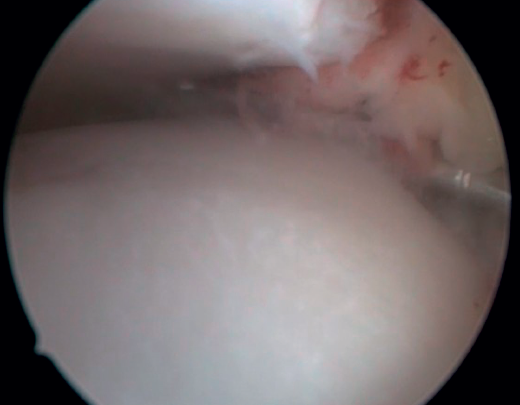

Arthroscopic diagnosis

The confirmation of AAI is made by direct vision during arthroscopic examination (Figure 4). This technique allows us to visualise the entire joint, assess the state of the articular cartilage and ligaments, detect the presence of capsular adhesions, synovitis, synovial thickening, loose bodies, etc. It also allows us to carry out functional tests to reveal possible associated instabilities or to assess how the soft tissues causing pain suffer impingement. In our experience, the presence of ATFL lesions is very frequent.